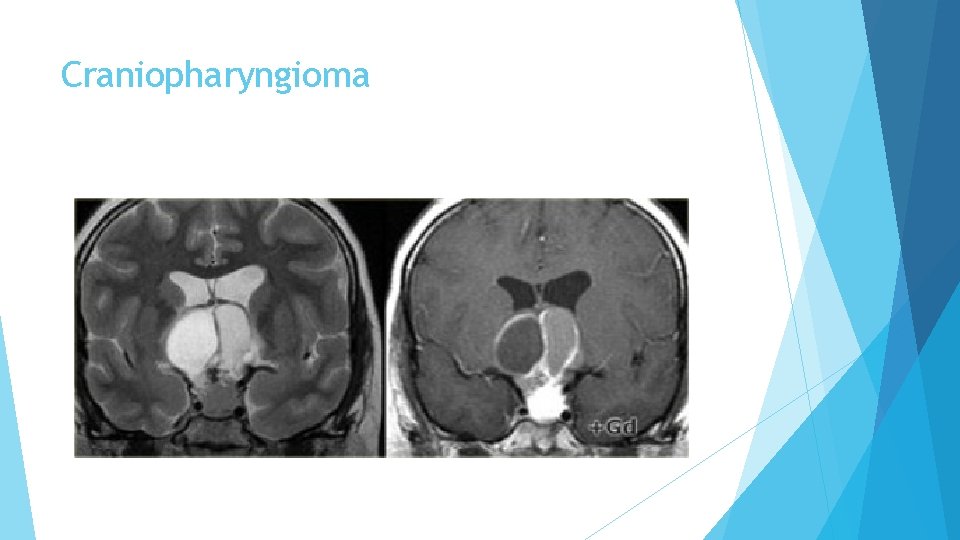

Craniopharyngioma is the third of the three pathologies derived from Rathke's cleft epithelium. Technically these are benign tumors, but unlike Rathke's cleft cysts, they have thick walls and are locally invasive. Macroscopically, it is a complex mass with multiple nodules at the base of the brain, sinuating along the fissures. Often, it can not be completely resected.

Craniopharyngioma In over 50% of cases craniopharyngiomas have a pathognomonic appearance. A compressed pituitary gland can be identified. There is a large intrasellar and suprasellar mass with cystic and enhancing components as well as calcifications. These findings in a child are virtually pathognomonic for craniopharyngioma (perhaps with only a dermoid in the differential diagnosis).

Craniopharyngioma